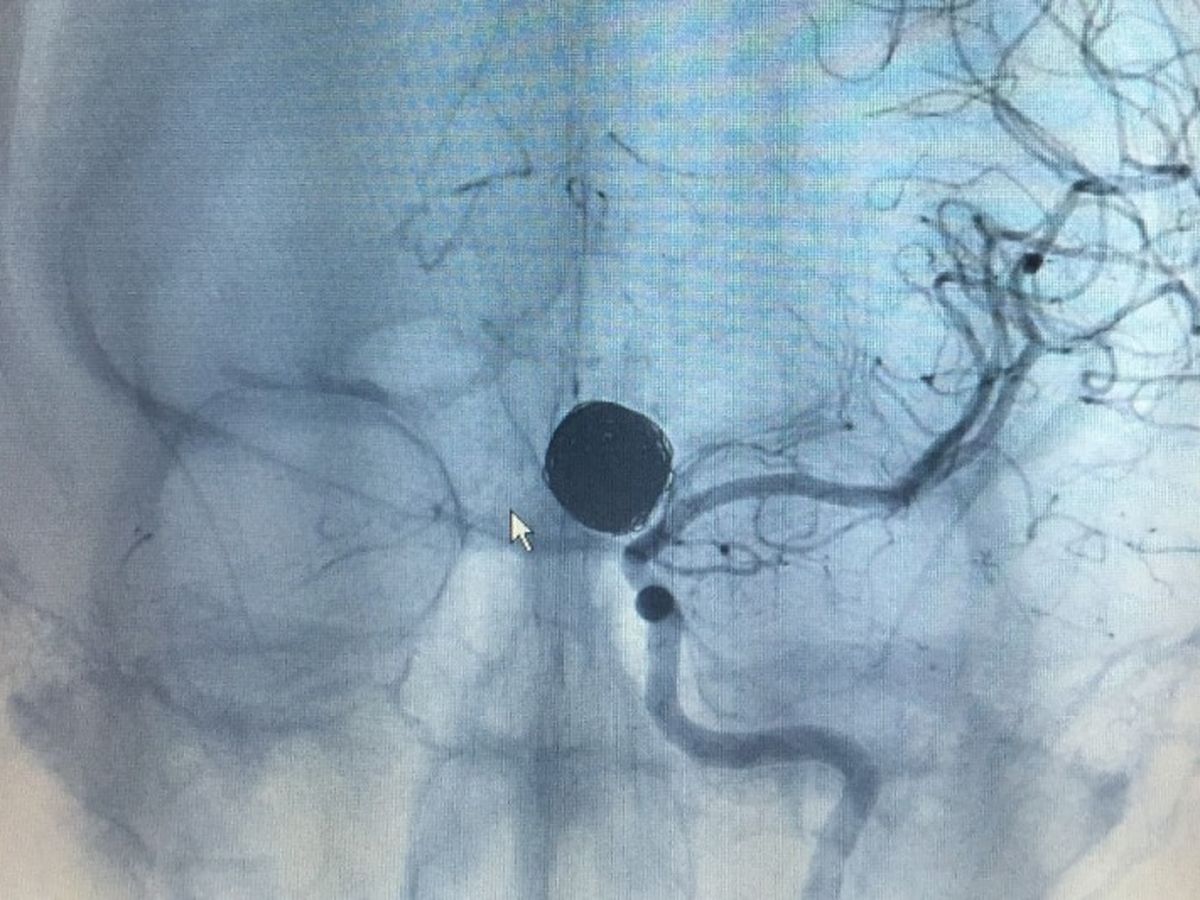

Late evening, on December 13, 2014 my 23 year old, pregnant daughter suffered a ruptured brain aneurysm in Saint Marys, GA. The ambulance took her to Camden County Hospital emergency room for CAT scan. Savannah was then immediately life-flighted to a Neuro Specialty Surgical Center at Baptist Hospital in FL, where she spent 12 days in ICU following brain surgery. Discharged from the hospital on Christmas Day, Savannah's recovery has been miraculous, with no permanent mental or physical damage. She and her husband, Kevin had just purchased their first home together in October 2014. The medical bills are begininning to pile in. As a young married couple with a one year old son and a baby girl on the way, the Steele family could really use some financial assistance for expenses not covered by their insurance. Please consider giving to our Christmas Miracle.